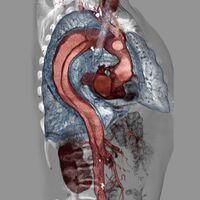

| Dissection of the descending part of the aorta (3), which starts from the left subclavian artery and extends to the abdominal aorta (4). The ascending aorta (1) and aortic arch (2) are not involved in this image. | |